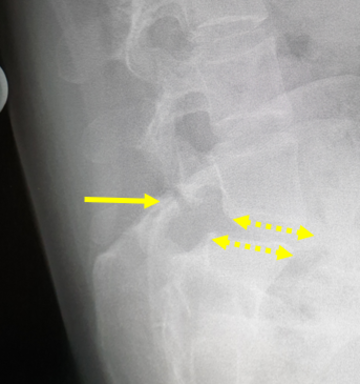

Schnell voranschreitende doppelbogige Skoliose bei einem 17 Jahre alten Mädchen. Beachten Sie die Beckenverkippung (rote Linie) und zusammenstehenden Rippen (roter Pfeil).

Zusätzlich zeigt sich eine Unterbrechung in den Wirbelgelenken (gelber Pfeil) mit einem zusätzlichen Wirbelgleiten (gestrichelte Pfeile) und hieraus bedingten Schmerzen der unteren Lendenwirbelsäule.